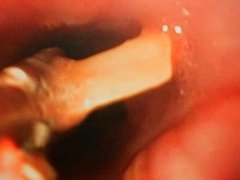

Bác sĩ mổ bất ngờ phát hiện miếng nhựa xuyên đường thở bé trai

Khỏe - 23/03/2019 07:40

Gia đình không biết bé trai 11 tháng tuổi nuốt dị vật, phim X-quang trước mổ cũng không phát hiện bất thường.